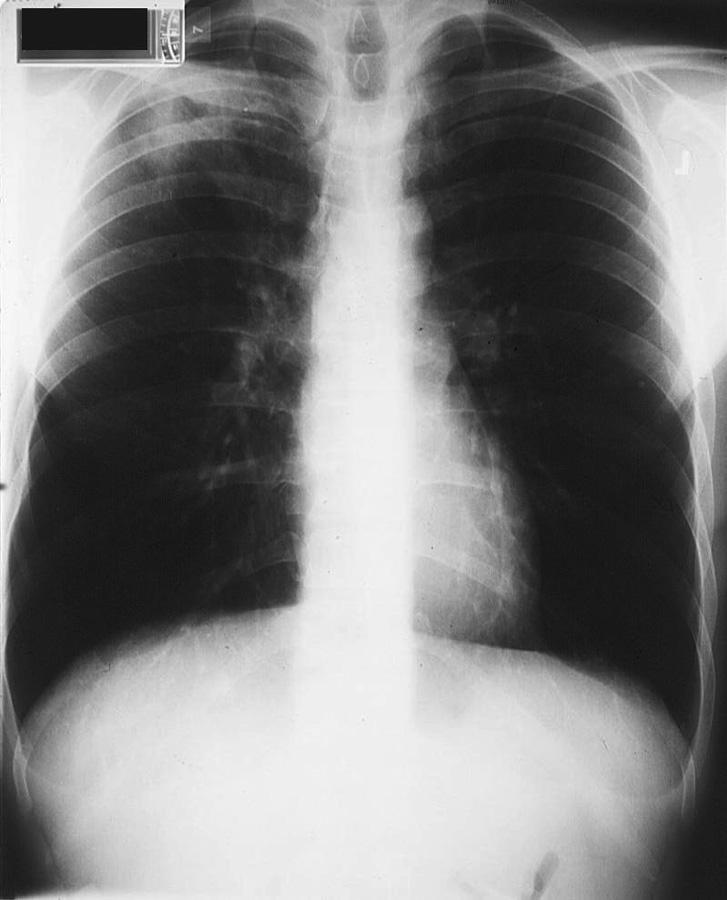

图5 胸部X线片显示肺脓肿的气液平面特征

图6 患者54岁,咳嗽

,咳痰异味。胸部X线片显示左下叶上段肺脓肿

在胸部X线片上,肺脓肿表现为孤立的空洞,具有气液平面。周围斑块状浸润有助于区分肺脓肿与空洞性肺癌。

在胸部X线片,发现脓胸而不是肺脓肿的气液平面向胸壁延伸,气液平面跨过肺裂延伸,并逐渐变细。

胸部X线片上应仔细检查肋膈角,以评估预示积液或脓胸的液体是否出现。

患者直立位胸片,当大约200 mL积液时,肋膈角变钝。

患者侧位胸部X线片显示胸膜液是否可移动并分层或是否限于局部。